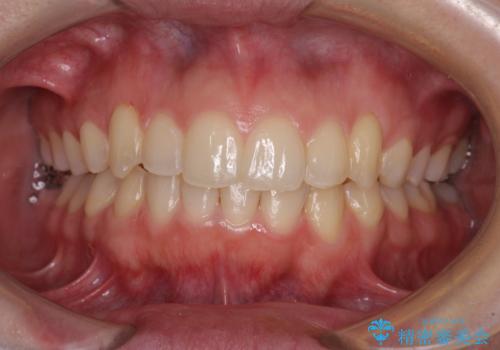

骨格的に左右にずれいている 前歯のデコボコをインビザラインで解消

- 3年3ヶ月

右側の咬合改善を目標に様々な手法を用いましたが、骨格的なズレによる不正咬合はインビザラインでは改善することができませんでした。